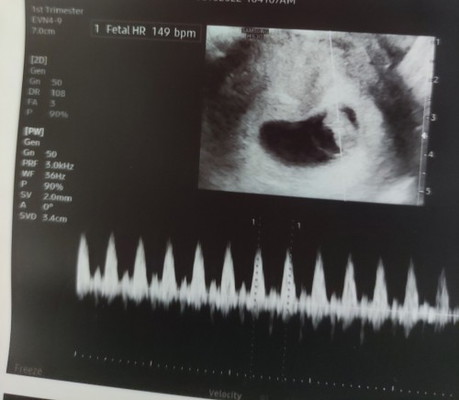

10 weeks 6 days ako kahapon, ultrasound na po ginawa. nung 6 weeks, trans v.